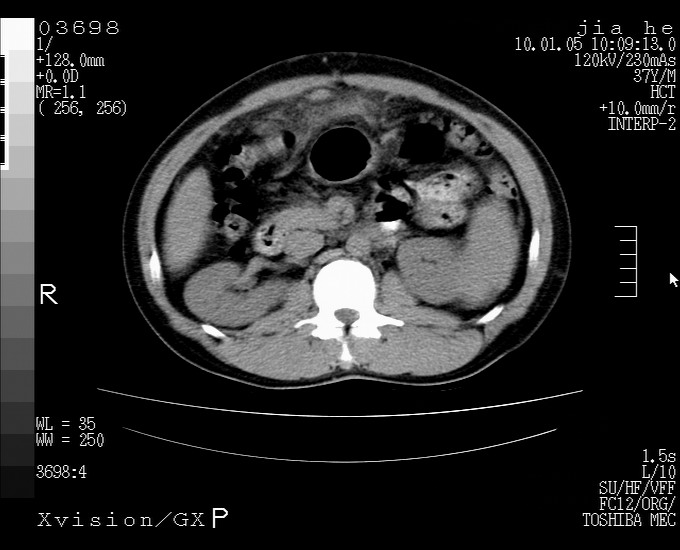

标题: CT23988:男,40岁,B超提示腹部肿物,请各位老师给看看。 [打印本页]

标题: CT23988:男,40岁,B超提示腹部肿物,请各位老师给看看。

肝癌并腹膜后淋巴西结转移

1.该患者有腹部手术史

2.脾大,肠系膜密度增高,有多发索条影,胰腺边缘毛糙,腹膜增厚,推测有肝硬化,门脉高压,腹膜炎和/或胰腺炎

3.肝左叶巨大站位,并腹腔淋巴结肿大,肝癌或肝间叶来源恶性肿瘤,也不排除大网膜间质瘤侵及肝左叶

建议:增强或磁共振

肝癌并腹膜后淋巴结转移

外生性肝癌并腹膜后淋巴西结转移!

肝硬化、脾大;胃底静脉曲张;是否门脉高压所致,建议进一步检查。

考虑肝左叶外侧段癌并腹膜后淋巴结转移.建议增强进一步检查.